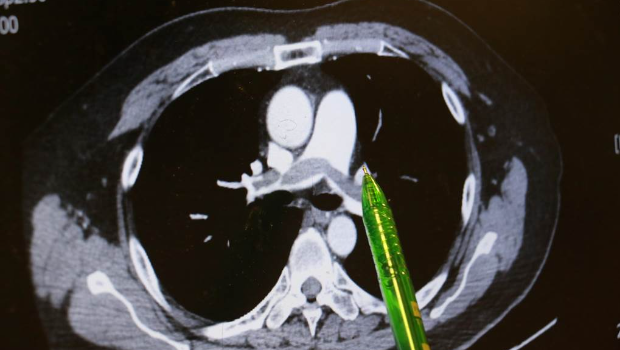

病人肺部?jī)蓚?cè)大片彌漫的血栓。

▲病人肺部?jī)蓚?cè)大片彌漫的血栓。臺(tái)中慈濟(jì)醫(yī)院提供

謝姓男子不煙不酒,他自述上班久坐、在家也習(xí)慣久躺沙發(fā),回想發(fā)病當(dāng)天走樓梯時(shí),短短一層樓竟像爬長(zhǎng)陡坡,路過同事見他喘不過氣、唇色發(fā)綠、冷汗直冒,催促緊急就醫(yī)。臺(tái)中慈濟(jì)醫(yī)院急診醫(yī)師檢查發(fā)現(xiàn)患者血氧飽和度指數(shù)極低,電腦斷層顯示雙側(cè)肺動(dòng)脈都有大塊血栓,會(huì)診心臟內(nèi)科主任林茂仁確認(rèn)是“雙側(cè)肺栓塞(Pulmonary embolism)”。

林茂仁說明,患者兩側(cè)肺葉彌漫大片血栓,屬于臨床典型而嚴(yán)重的“肺栓塞”,幸好他馬上到急診就醫(yī),還主述一周前曾出現(xiàn)“單側(cè)小腿腫脹”的重要訊息,再透過相關(guān)檢查,幫助醫(yī)師快速查出病因。由于患者血液檢查發(fā)現(xiàn)具有家族性先天凝血因子異常,顯示體質(zhì)天生比一般人有更多發(fā)生血栓的機(jī)會(huì)。